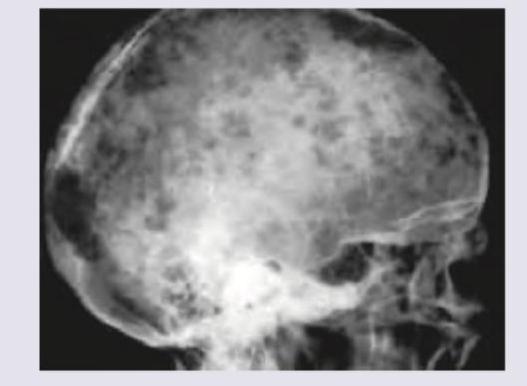

Question 22: X-ray skull shows: (Recent NEET Pattern 2016-17)

- A. Multiple myeloma

- B. Histiocytosis-X

- C. Letterer-Siwe disease

- D. Silver-beaten appearance (Correct Answer)

Explanation: ***Silver-beaten appearance*** - The image shows a skull with multiple **gyral impressions** on the inner table, giving it a **bumpy**, 'silver-beaten' or 'copper-beaten' appearance. - This pattern is classically associated with **chronically increased intracranial pressure**, which causes the brain's convolutions to press against the skull. *Multiple myeloma* - Multiple myeloma typically presents with multiple, sharply demarcated **"punched-out" lytic lesions** in the skull, not diffuse gyral impressions. - These lesions often lack a sclerotic rim and are more discrete than the pattern seen here. *Histiocytosis-X* - Histiocytosis-X (now called Langerhans cell histiocytosis) can cause lytic skull lesions, often described as **"beveled edge"** or geographically distributed lesions. - While it can cause osteolytic bone destruction, it does not typically produce the widespread, uniform gyral impressions of a silver-beaten skull. *Letterer-Siwe disease* - Letterer-Siwe disease is an aggressive, disseminated form of **Langerhans cell histiocytosis** affecting infants. - While it can cause bone lesions, including in the skull, it typically manifests as generalized lytic lesions rather than the "silver-beaten" pattern indicative of chronic elevated intracranial pressure.